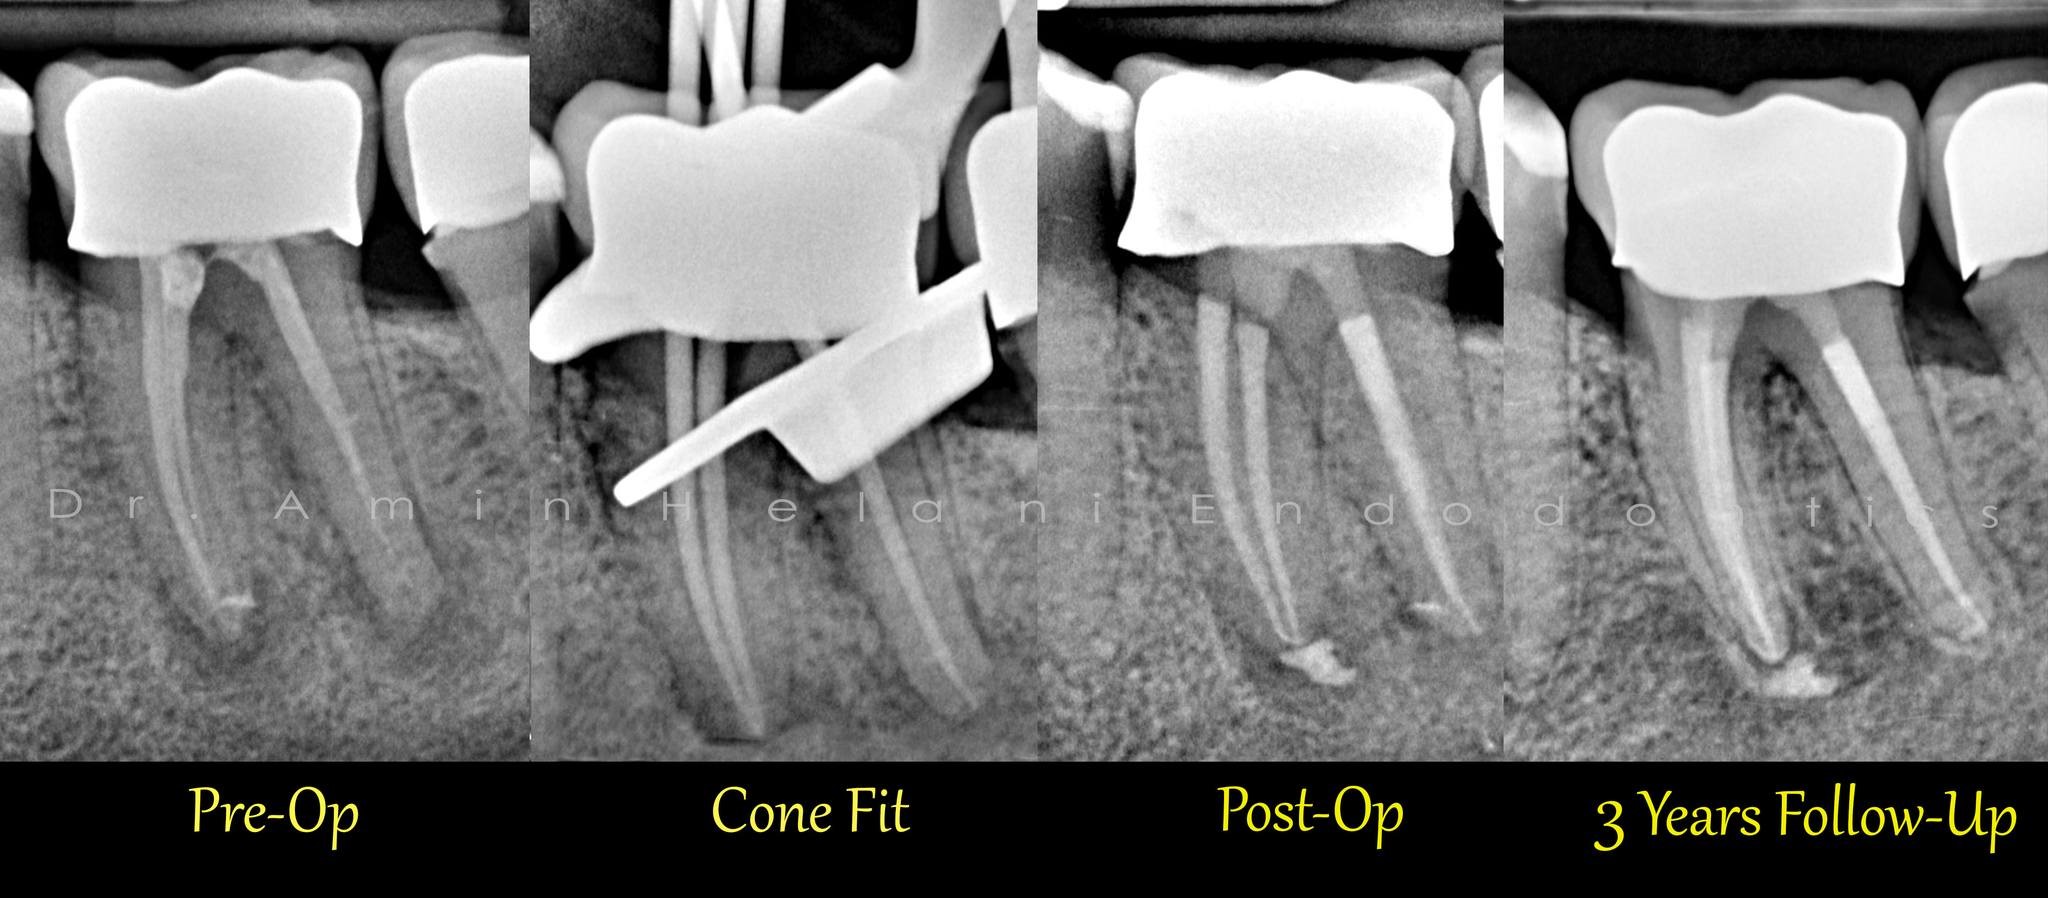

Seitenkanal + Heilung